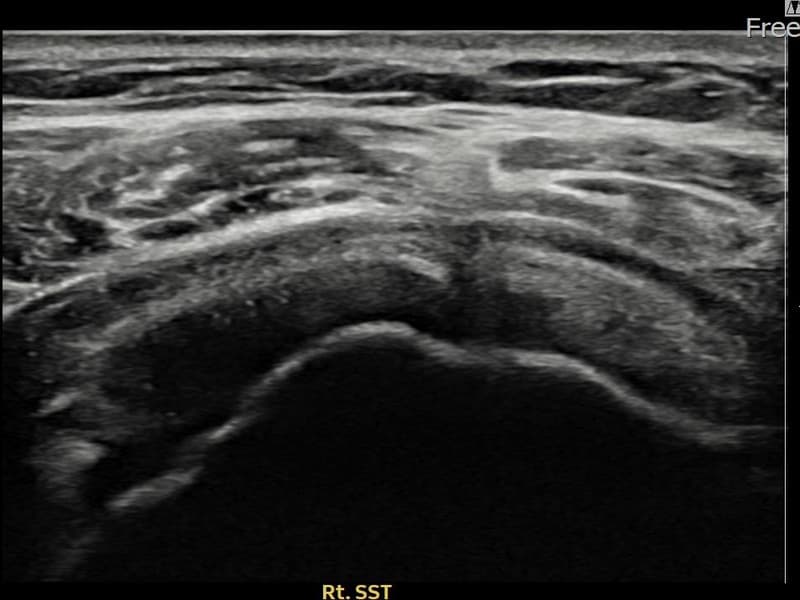

超音波検査にて右 棘上筋腱 関節面側部分断裂(7mm × 3mm (腱厚の約30%欠損))を確認。縫縮術施行後、腱の連続性が回復し、日常生活に復帰されました。

施術前

術前超音波にて右 棘上筋腱 関節面側部分断裂・右肩棘上筋腱のエコー不連続と腱欠損(7mm × 3mm (腱厚の約30%欠損))を確認。術後超音波では断裂部位が再生組織で充填され、腱の連続性回復とエコーパターンの正常化が確認されました。

持続する右肩痛で来院された患者様です。超音波検査にて右 棘上筋腱 関節面側部分断裂(欠損:7mm × 3mm (腱厚の約30%欠損))を確認し、超音波ガイド下で非手術的縫縮術を施行しました。術後は約4〜6週間のブレース装着の後、段階的なリハビリプログラムを実施。経過超音波で腱の連続性回復を確認し、患者様は無事に日常生活へ復帰されました。